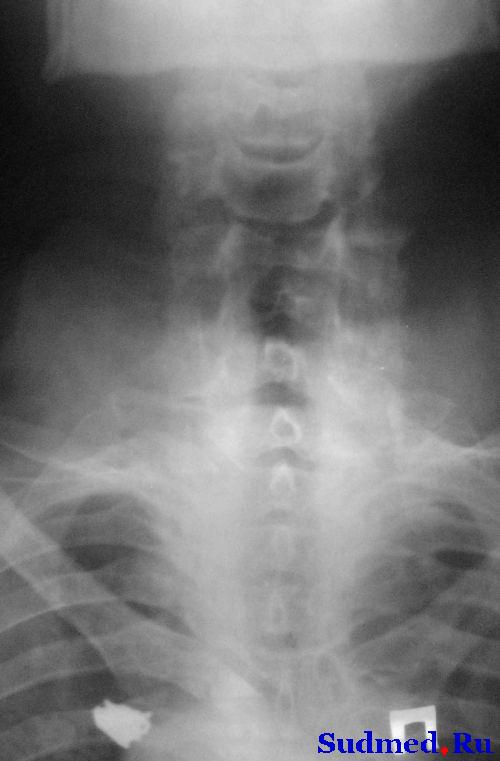

описание снимков такое : На рентгенограммах шейного отдела позвоночника в 2-х проекциях определяется вывих С4 кзади на ½ диаметра тела позвонка, со сдавлением позвоночного канала на ¾ диаметра. Признаки остеохондроза шейного отдела позвоночника С2-С3, С№-С4, С4-С5, С 5-С6 2 степени.

В протоколе операции повреждение задней связки не описано. На вскрытии тмо не вскрыта, спинной мозг с кровоизлиянием размягчен, задняя продольная связка(идет по задней поверхности тела позвонков в спиномозговом канале - ? если не путаю) отслоена от тела 4 позвонка.

рентген, наконец-то выложил

Эскизы прикрепленных изображений

Судебная медицина - Прикрепленное изображение

с меньшими шумами

Судебная медицина - Прикрепленное изображение Судебная медицина - Прикрепленное изображение